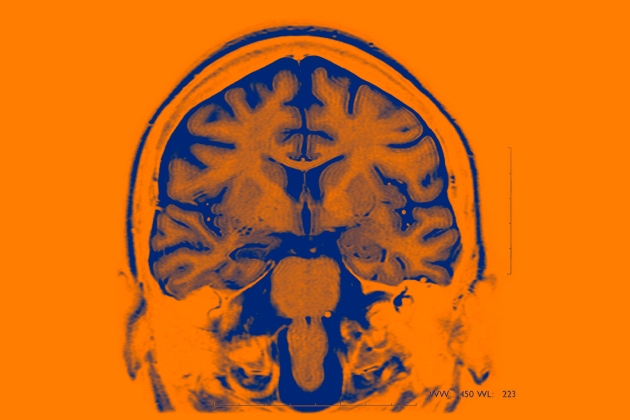

据《自然》（Nature）网站报道，美国国防部高级研究计划局（DARPA）资助的研究团队正在开发设备来记录神经活动和自动刺激大脑，该设备主要用来治疗精神疾病。由AI控制的、针对情绪障碍的大脑植入物目前在进行人体试验。<br />

可针对人的情绪和行为提供电脉冲的大脑植入物，目前首次在人身上进行试验。DARPA资助的两个团队已经开始展开&ldquo;闭环&rdquo;大脑植入物的初步试验，植入物使用算法来检测与情绪障碍相关的模式。<br />

这些设备能够刺激大脑恢复到健康状态，无须医生亲自实施刺激。<br />

这项最近在华盛顿特区的神经科学学会（SfN）大会上展示的研究，最终可能会带来目前难以治疗的严重精神疾病的方法突破。同时它也引起了棘手的伦理道德问题，尤其考虑到该技术可能会让研究人员能够在一定程度上实时了解到人的内心情感。<br />

一般的方法&mdash;&mdash;利用大脑植入物提供电脉冲来改变神经活动&mdash;&mdash;被称作脑深部电刺激术。它被用于治疗帕金森症等活动障碍，但在治疗情绪障碍的试验中效果并没有那么好。早期的证据显示，持续性刺激脑部的特定区域会缓解慢性抑郁，但一项涉及90位抑郁症患者的大型研究发现，治疗一年以后患者病情并无改善。<br />

DARPA资助的项目背后的科学家表示，他们的研究可能会在之前的尝试失败的地方取得成功，因为他们的大脑植入物是专为精神疾病治疗而设计的&mdash;&mdash;而且只会在需要用到的时候才会开启。&ldquo;我们对于现有的技术的局限性有了很多的了解。&rdquo;加州大学旧金山分校（UCSF）领导其中一个项目的神经科学家爱德华&middot;常（Edward Chang）说道。<br />

DARPA在支持爱德华&middot;常的研究团队以及另一个在波士顿的麻省总医院的研究团队，最终目标是治疗患有抑郁症和创伤后应激障碍的士兵和退伍军人。两个团队都希望打造一个植入电极系统，来跟踪大脑被刺激时其各个部分的活动。<br />

他们正在面向癫痫症患者的试验中开发他们的技术，那些患者已经在大脑中植入跟踪其癫痫发作情况的电极。研究人员能够利用那些电极记录患者大脑在被间歇性刺激时的情况&mdash;&mdash;没有进行持</p>